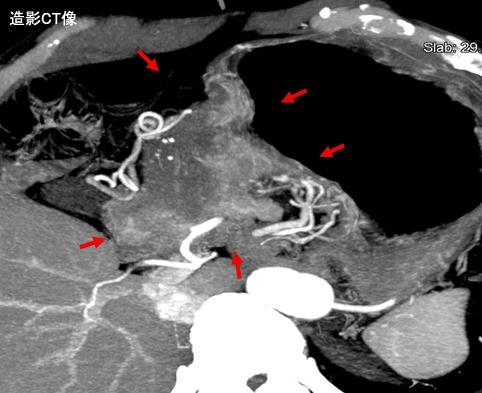

A case of type 4 advanced gastric cancer which developed in the antrum and was diagnosed by multidisciplinary method.

Tumor Epitelial Maligno/Carcinoma Mucinoso

parte(separada por órganos)

estómago(región)/antro

TAC

Tipo 4(Tipo difusamente infiltrado)/

diámetro mayor del tumor

40 -

s(a)